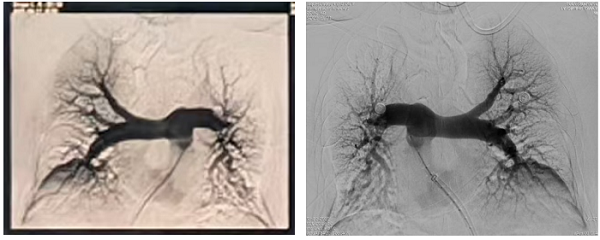

QQ20250912-195426

术后造影双侧主干未见明显血栓

术后,患者肺动脉压力从60mmHg降至35mmHg,氧饱和度恢复至96%。患者恢复健康后已出院。